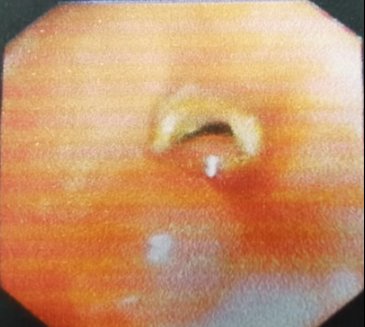

▲右下叶基底段异物嵌顿并肉芽包裹

术中,见患者的右下叶有异物嵌顿,周围大量肉芽样组织包裹,支气管远端情况不明,医师蓝军用活检钳对周围的肉芽进行仔细清理,娴熟地剥离出异物一端。随后用异物钳尝试钳取异物,但发现异物表面一碰就碎。“怎么办?难道一点一点夹碎了取出?”